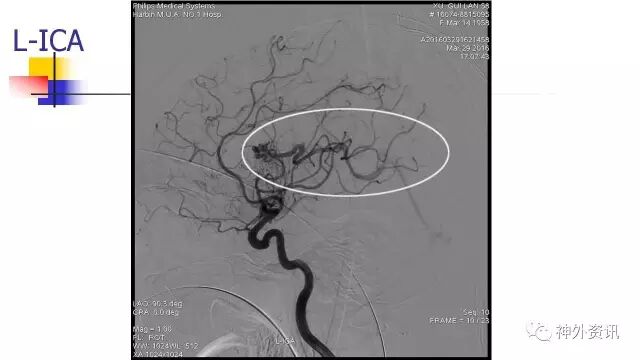

L-ICA正位动态